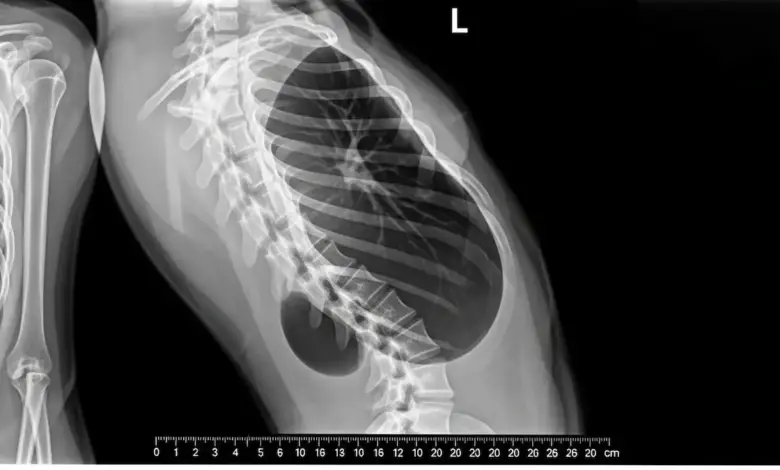

- Radiografias panorâmicas da coluna em pé, para medir o grau da curva e localizar a hemivértebra;

- Tomografia computadorizada, que mostra com precisão o formato das vértebras e a anatomia óssea;